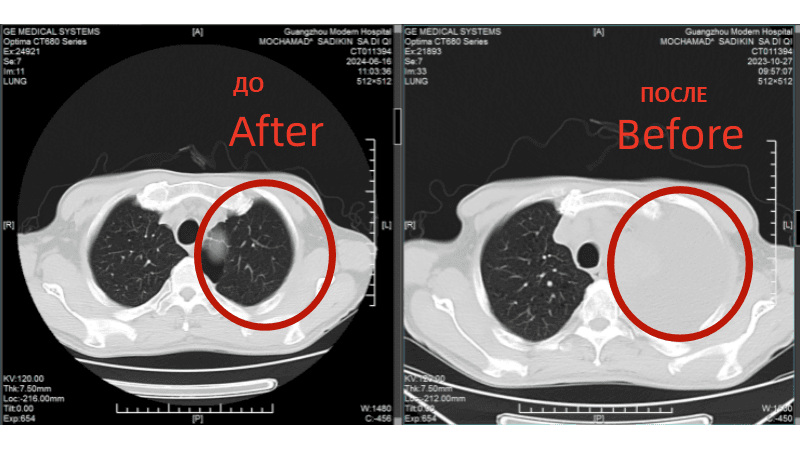

История надежды: Мохамад Садыкин из Индонезии побеждает рак легких IV стадии 68-летний пациент вернулся к активной жизни после комплексного малоинвазивного лечения в Гуанчжоу

В октябре 2023 года у Мохамада Садыкина из Джакарты появились тревожные симптомы: непрекращающийся кашель, одышка и лихорадка. Обследование выявило рак левого легкого IV стадии с метастазами в печень и плевральным выпотом. Новость шокировала семью: Мохамад потерял 24 кг за две недели, а врачи в Индонезии не предлагали эффективных вариантов. Но его жена не сдалась: «Я сказала мужу: мы сделаем всё возможное. Рак можно победить!»

Результаты: от отчаяния к теннису

• Через 2 курса лечения: Кашель и одышка уменьшились, метастазы в легких и печени значительно сократились. • Через 6 месяцев: Плевральный выпот исчез, вес вернулся к норме. • Июнь 2024: Мохамад отдыхал на Бали и играл в теннис.

КТ-снимки подтвердили: опухоль в легком практически исчезла